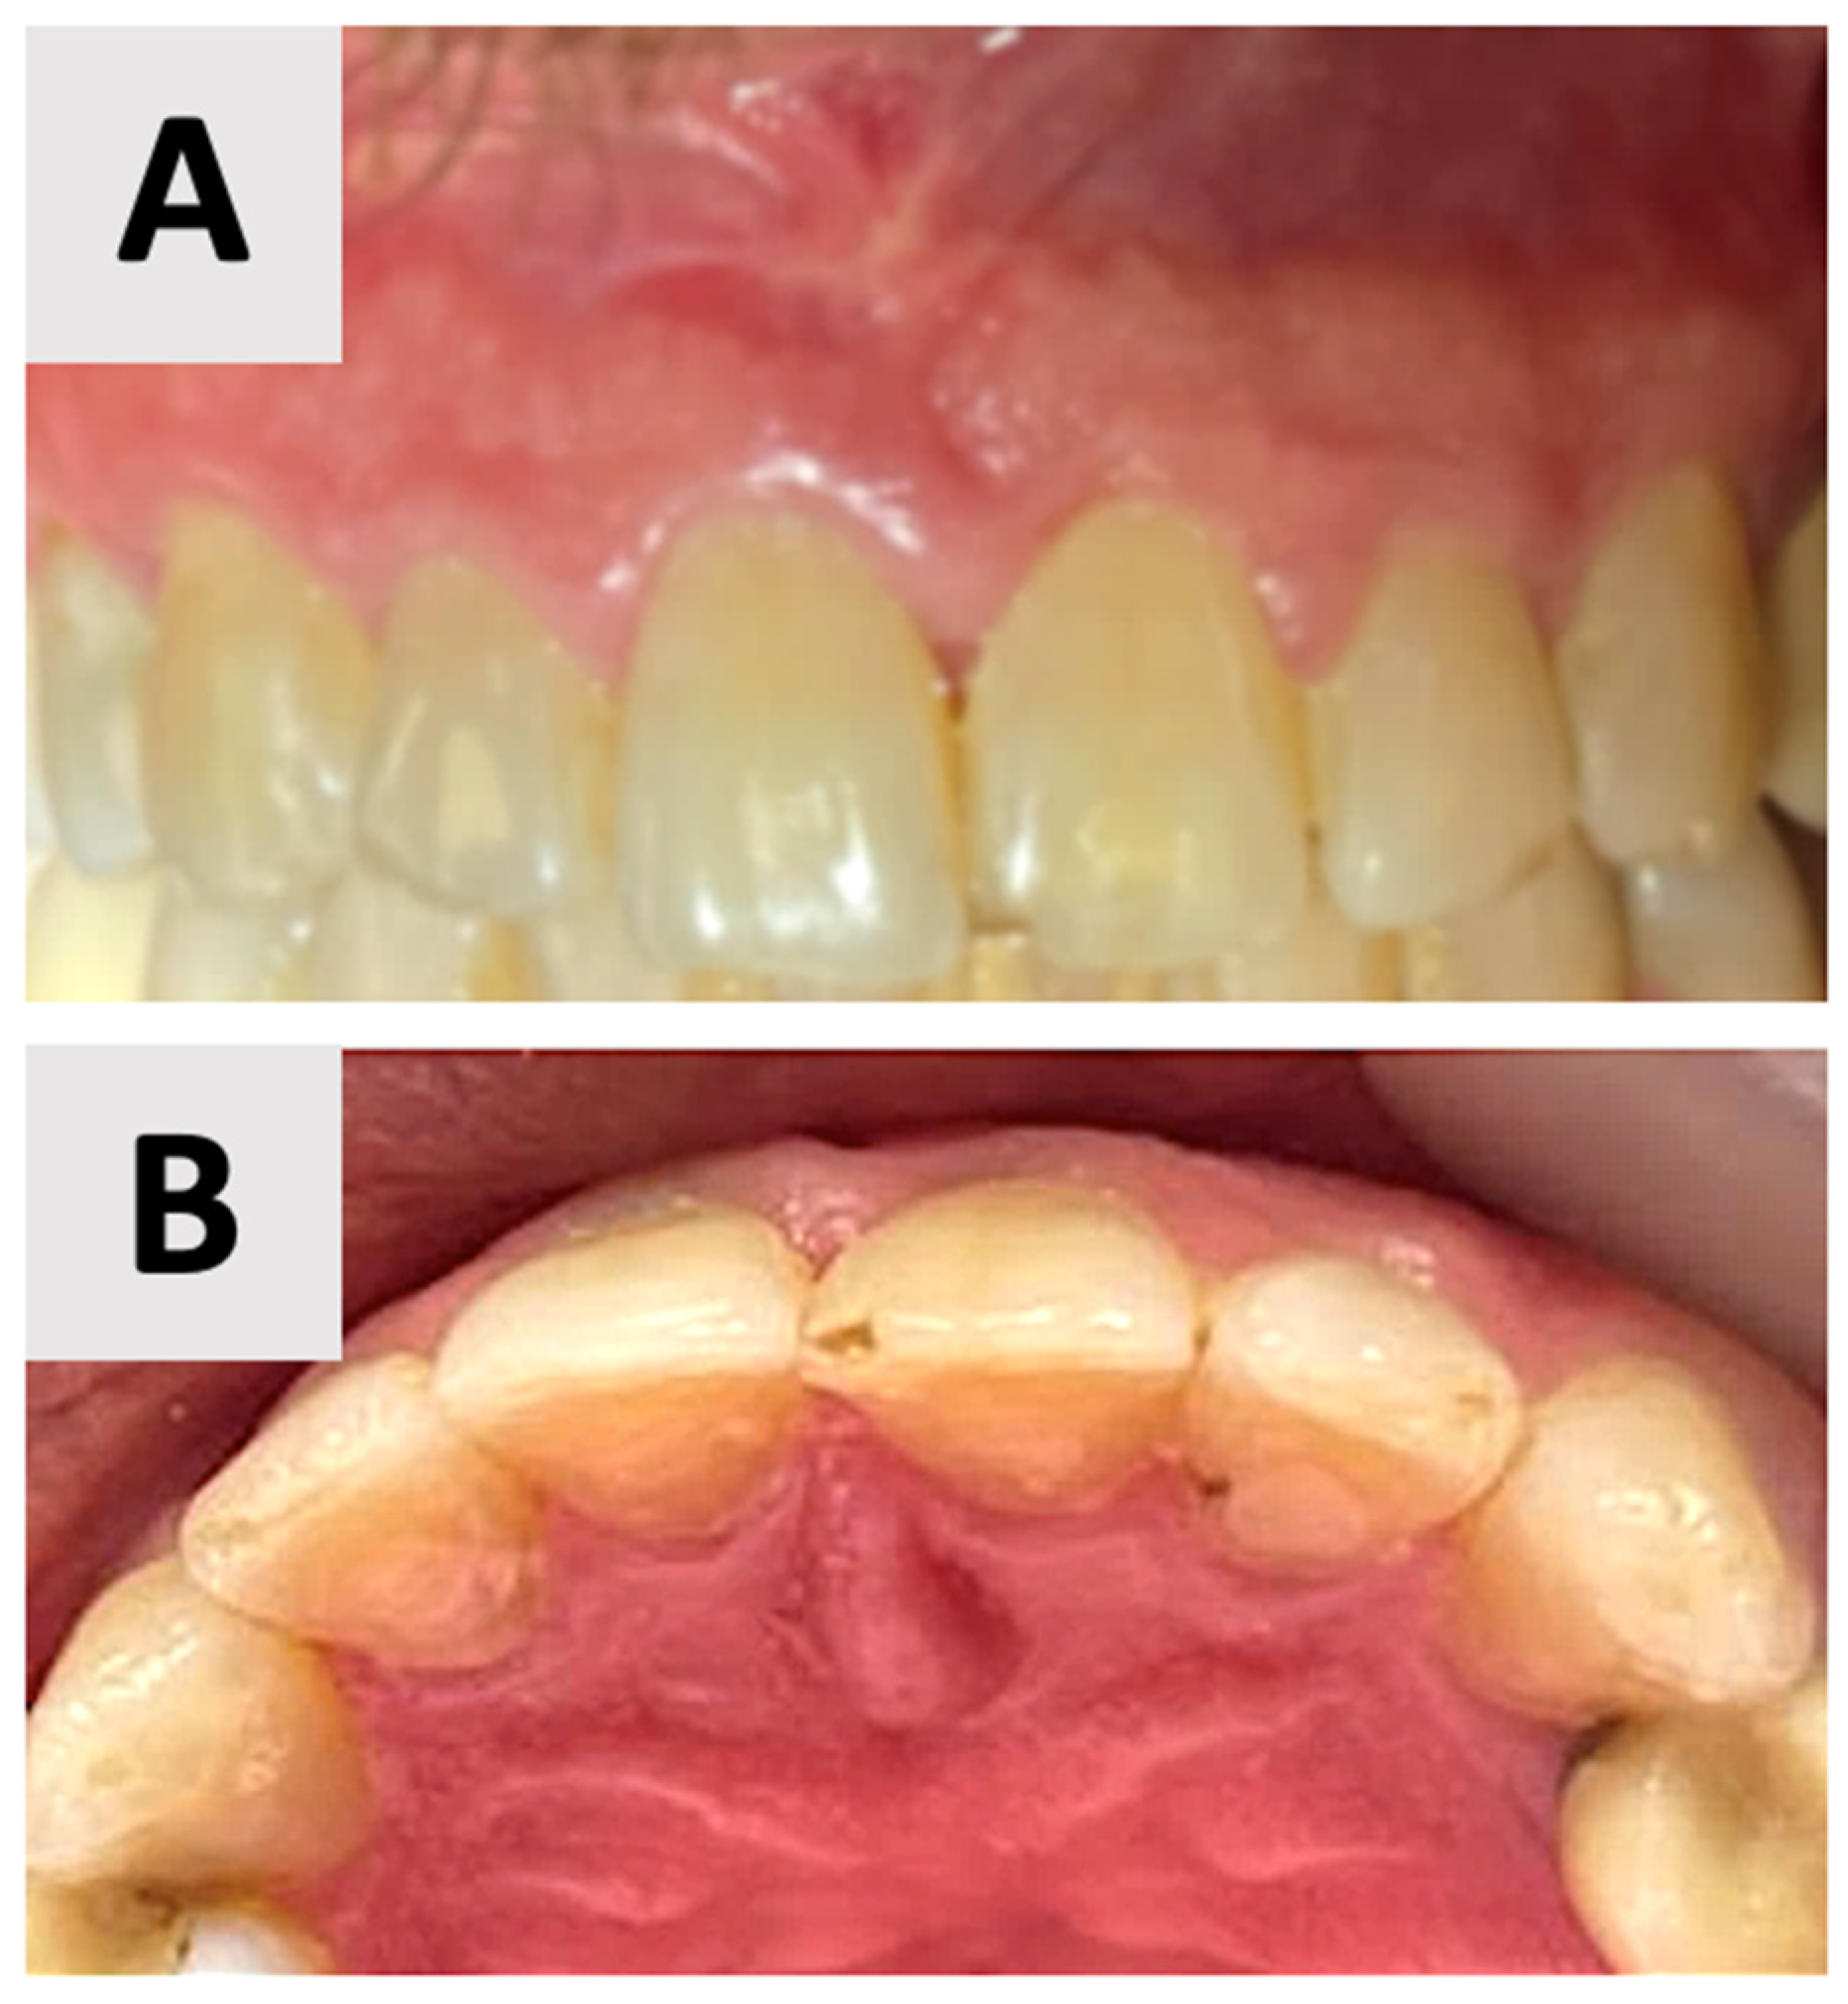

Clinical examination at 16 months post-augmentation revealed that the patient remained asymptomatic. The treated teeth exhibited no mobility. Both the alveolar bone and soft tissue contours were well-maintained, preserving the site’s architecture (Figure 8). The patient reported no functional limitations or esthetic concerns, further confirming the success of the procedure from both clinical and patient-centered perspectives.

Figure 8.

Clinical assessment at 16 months post-augmentation. (A) Facial view demonstrating optimal esthetic outcomes with well-preserved gingival architecture and natural tooth appearance. (B) Palatal view showing complete soft tissue healing and maintenance of anatomical contour.